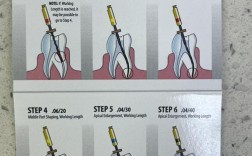

- 骨修整:

- 核心步骤! 使用高速涡轮机球钻或骨凿/骨锉,根据术前设计(通常需要暴露至少3-4mm的健康牙体组织,并确保最终龈沟底在生物学宽度之上)修整牙槽骨。

- 对于单颗牙,修整呈“碗状”或“梯形”,即邻骨高度保留,中央骨嵴降低。

- 对于多颗牙,修整呈“波浪状”,保留邻间骨嵴,降低中央区域骨高度。

- 必须保证: 新形成的牙槽嵴顶到最终预期的龈沟底的距离至少为2mm(生物学宽度)。